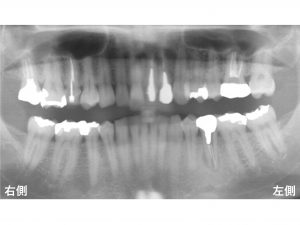

早速初診時のレントゲンから見てみましょう!

下顎左側の奥から3番目の歯の歯肉が腫れるとのことでした。

診査の結果、

この歯は歯根破折 していました。